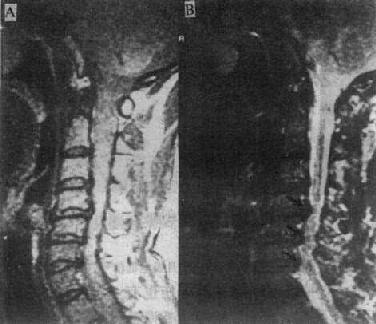

MRI可清楚地显示椎管狭窄,包括椎体与脊椎小关节的增生、韧带肥厚和椎间盘脱出等。如果椎间盘脱出发生在多个平面,且相对的黄韧带肥厚,则在与椎间隙水平相对应的硬膜囊前后缘受压,在矢状面T2WI上,硬膜囊呈串珠状表现(图2-2-4)。

质子密度像 T2WI

图2-2-4p; 颈椎关节病颈4~6段的蛛网膜下腔及脊髓于椎间盘水平均受压变细,呈典型的糖葫芦状